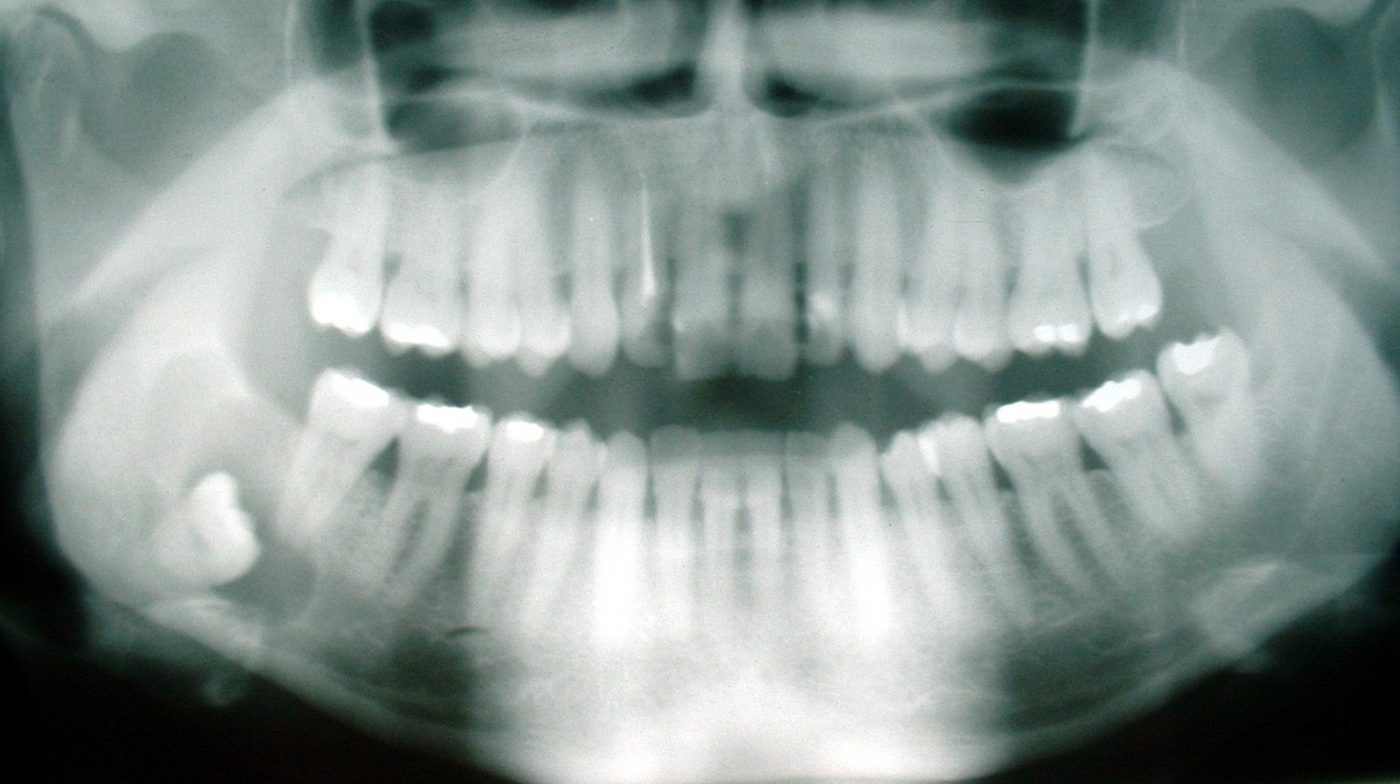

Mens Sverige gjeninnfører alderstesting, avslutter Universitetet i Oslo samarbeidet med Det odontologiske fakultet om medisinsk aldersfastsettelse. Medias dekning av saken er påfallende ensidig, og alderstester blir konsekvent kalt "kontroversielle" med "stor feilmargin". Stemmer dette? Og hvorfor er alderstesting så viktig at selv det berøringsangste Sverige nå gjeninnfører det?

Mens Sverige gjeninnfører alderstesting, avslutter Universitetet i Oslo samarbeidet med Det odontologiske fakultet om det media konsekvent kaller "kontroversielle alderstester" med "stor feilmargin". Før jul trakk firmaet Barnesak seg ut av avtalen med UDI da den pensjonerte barne- og overlegen Jens Grøgaard fikk kritikk fra Rådet for legeetikk. Men hvem er kritikerne, og er testene kontroversielle fordi de faglig sett har stor feilmargin - eller skyldes den angivelige faglige kritikken noe annet? Historien om hva som skjedde med UiOs samarbeid kaster et visst lys over saken.